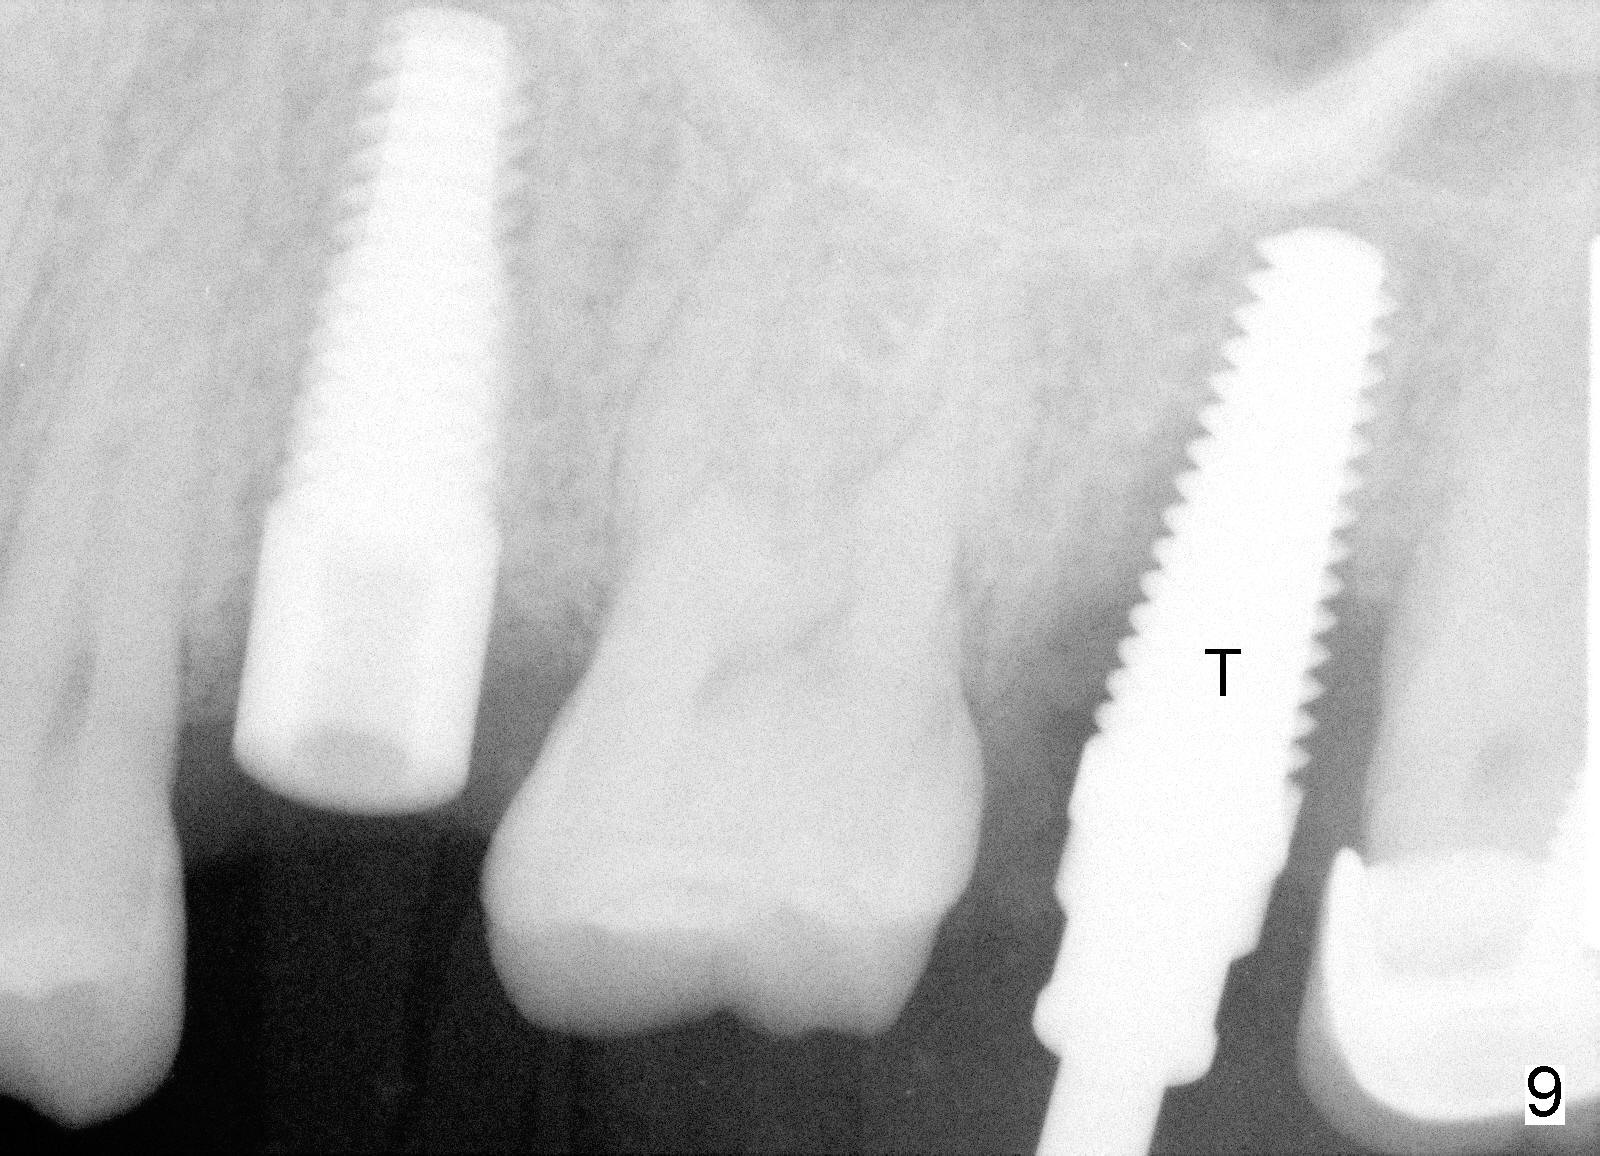

A 43-year-old lady has multiple nonsalvageable teeth. The first surgery involves two immediate implants in the upper left sextant (Fig.1: #13 and 15). The tooth #15 has 3 residual roots (MB, DB, P). There is no septum left between the first two roots when the tooth is extracted. A septum exists between the palatal (P) and buccal (B) sockets (Fig.2). Bone expansion technique is utilized to create an osteotomy in the septum. However, the smallest rounded tapered osteotome cannot be driven into the narrow septum; it slides (Fig.5). To get an initial engagement, a slot is created by high-speed surgical handpiece and fissure bur on the top of the septum. A series of blade-like osteotomes are inserted into the septum for sectioning (Fig.2 >). The smallest rounded osteotome is now easy to be inserted into the middle of the septum (Fig.3 circle, Fig.6 O). The septum is expanded by larger osteotomes (Fig.4 white circle; Fig.7 O) and tap (Fig.9 T). The septum continues being expanded when a 6x14 mm implant is placed (Fig.8,10 I). The insertion torque is more than 60 Ncm. No bone graft is placed. The palatal gap is closed by a palatal flap.